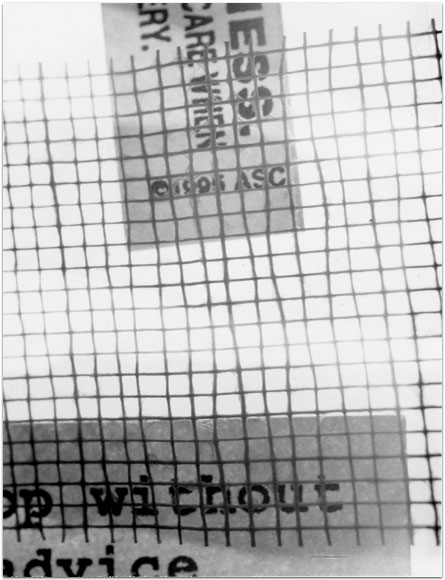

- Itis

- 2004

- 3.25″ × 4.25″

- Photographic montages of my hands & health paraphernalia on Polaroid Type 664 & 669 Film using a Daylab Printer.

- Frustrated by a lack of mobility and severe pain with my fingers, unable to accomplish any task requiring joint dexterity,

I noticed piles of health related papers strewn around. I layered these in a slide printer without removing

my hands, enlarging both onto the film.